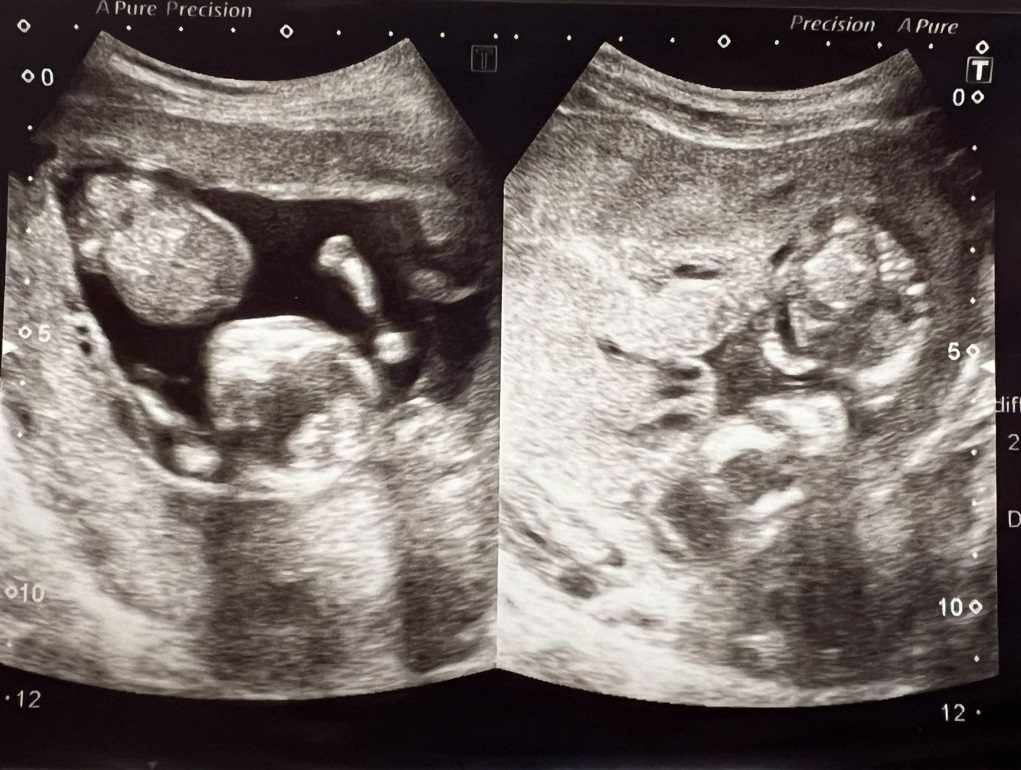

羊水がほぼない状態と診断された日のエコー写真 (@keroppi__keroppiさんより提供)